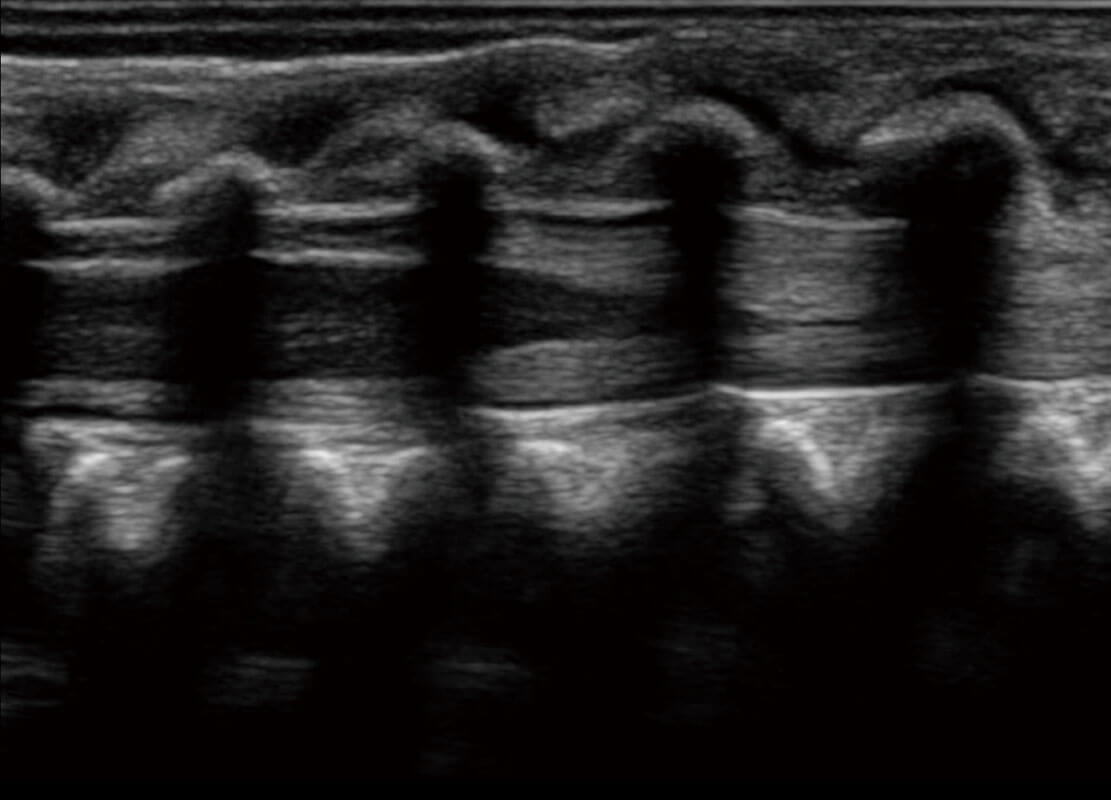

新生兒肝血管癌

新生兒脊髓圓錐

新生兒心臟

P60搭載寬頻帶線(xiàn)陣探頭、寬景成像、彈性成像技術(shù),為您提供乳腺應(yīng)用方案。P60支持高頻相控陣探頭、線(xiàn)陣探頭、腹部高頻探頭、腹部微凸探頭等,豐富的探頭群搭載敏感的彩色血流成像,適用于新生兒多種臟器檢測(cè)要求,滿(mǎn)足新生兒篩查需求。